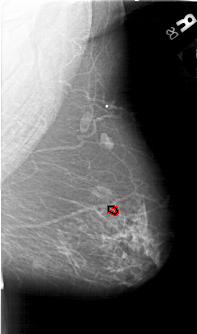

A_1646_1.LEFT_MLO

LEFT_MLO LINES 6871 PIXELS_PER_LINE 3751 BITS_PER_PIXEL 12 RESOLUTION 43.5 NON_OVERLAY

FILE: A_1646_1.RIGHT_MLO.OVERLAY

TOTAL_ABNORMALITIES 1

ABNORMALITY 1

LESION_TYPE CALCIFICATION TYPE PLEOMORPHIC DISTRIBUTION CLUSTERED

ASSESSMENT 3

SUBTLETY 2

PATHOLOGY BENIGN

TOTAL_OUTLINES 1

BOUNDARY